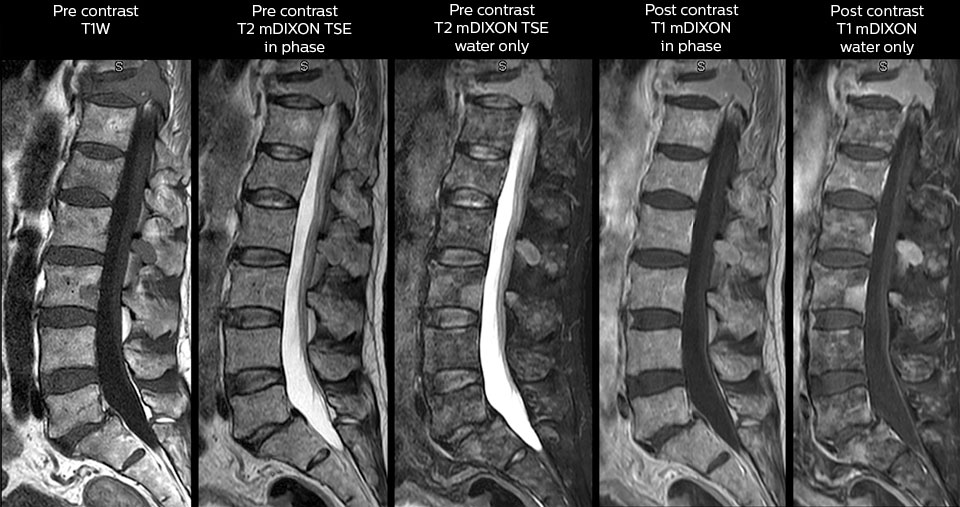

“We use mDIXON TSE extensively in our spine imaging in the emergency room,” says Dr. Karis. “It’s particularly nice in that it is very robust with regard to susceptibility type of problems that would come up with traditional spectral fat-saturated images; these problems are essentially eliminated with the mDIXON technique. In our ED environment it’s really nice to have the fat-free imaging that goes along with the mDIXON technique.

“For the thoracic and cervical spine routine non-contrast exam, for example, we perform one mDIXON T2 TSE sequence, which provides us with two outputs: the fat-and-water-together T2-weighted images, as well as the water-only sagittal T2-weighted images. And then we also perform an axial gradient echo exam.”